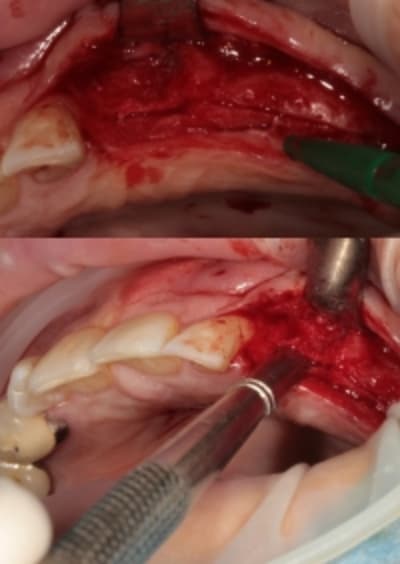

quand je fais du deux temps (expansion, comblement avec du biomat et intervention c'est parce que l'os est à sa limite et ne peut gérer une reconstruction et une ostéo-intégration.

Il s'agit alors d'os D1 ou de crête d'environ 1mm.

exemple:

autre exemple de deux temps:

expansion pose pour 35 et 37 et mise en attente pour 36 os D1 fracture provoquée.

désolé pour la qualité des photos

merci à D57 pour le "prêt" de son patient....

le troisième implant à été posé par Thomas il y a peu de temps (à 6 mois) avec un os très bon d'après lui.